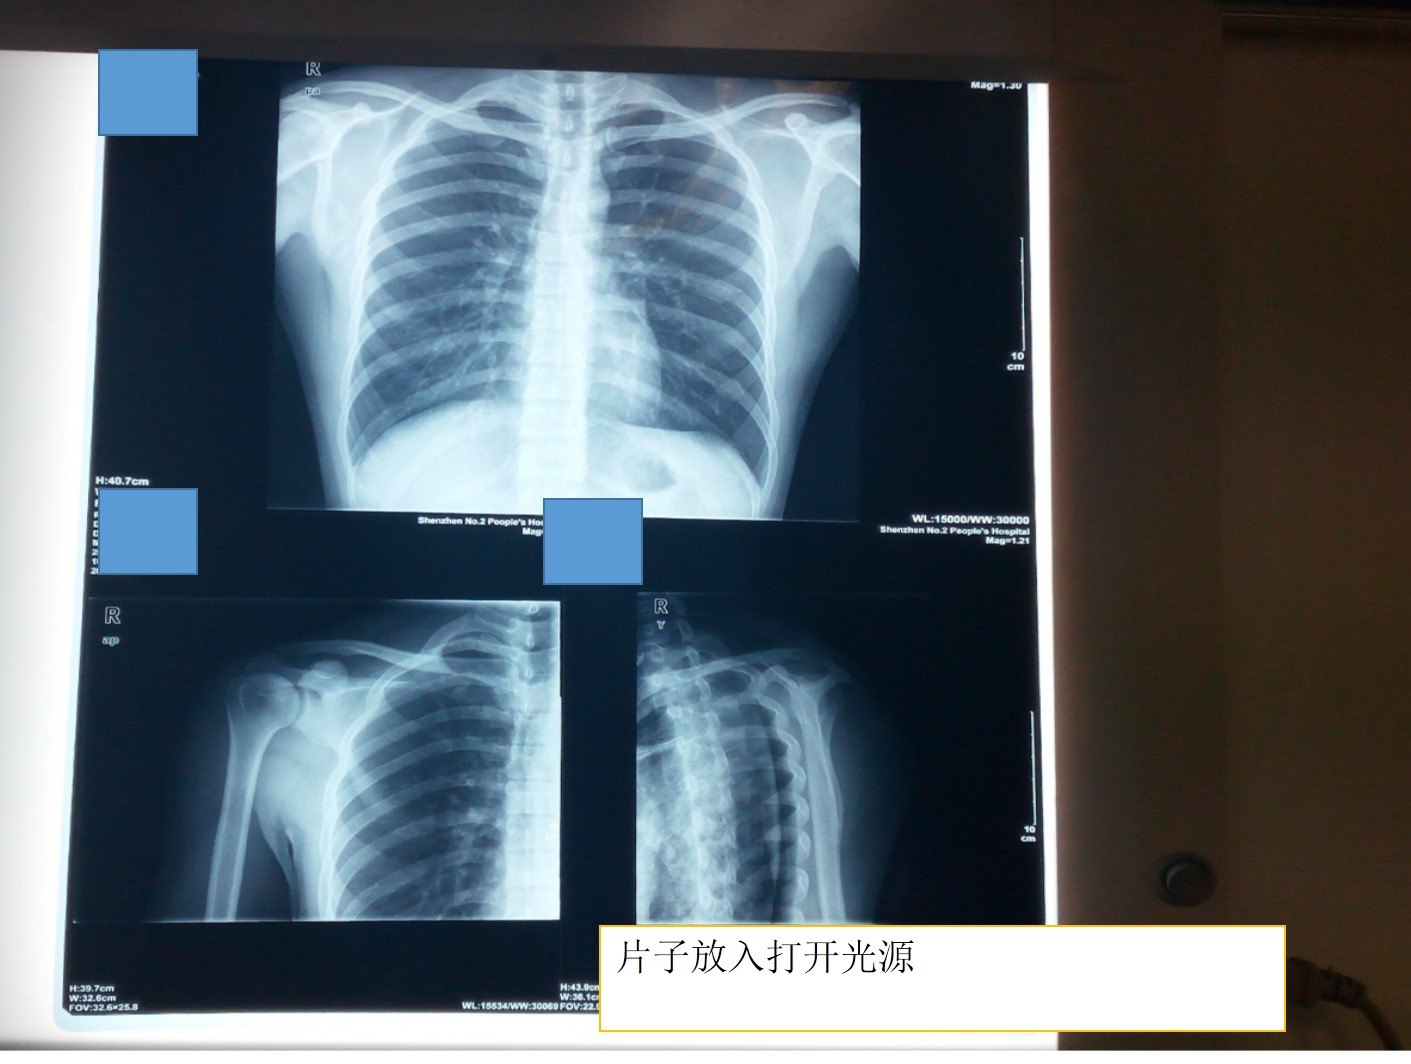

1.医院的阅片灯罩进行拍片

2.电脑显示器进行拍片 建立空白PPT--调整最大亮度---PPT放映 ----放片子拍照

3.使用玻璃窗户拍照 注意背景要白色,清晰

拍片子要:光线好,背景为白色,关闭散光,选择1个最多不超过4个窗口进行拍照。